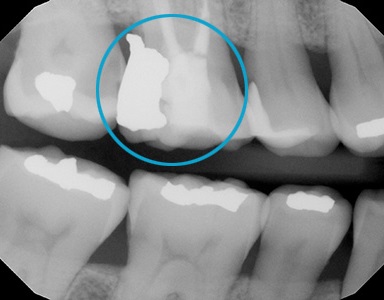

Amalgam Replacement

Replaces bad amalgam fillings with a tooth-like material. Restores the tooth to its original look. No red gum and trapping of food particles anymore. It provides a better appearance and better function.

Amalgam replacement with Cerec Onlay.

Creates long-lasting teeth by preserving more teeth structure in a biomimetic way!